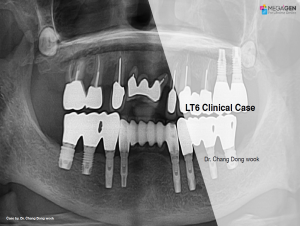

e.g. product name, treatment solution, author, clinician name